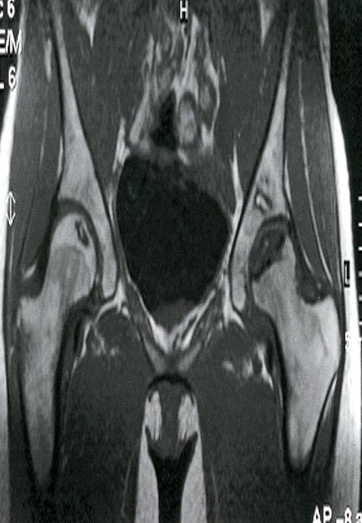

Bilateral osteonecrosis of the femoral head

MRI hips (T1 weighted; coronal view) of a 32-year-old

woman with groin pain

There is a well-defined crescent-shaped area of intermediate

to low signal within the subchondral marrow of the left

femoral head . On the right side, there is a slightly smaller

area of abnormal oval-shaped signal within the epiphysis of

the right femoral head.

Coronal MRI scan showing avascular necrosis of

both femoral heads. The changes on the left are

very severe and advanced. The changes in the right

hip are relatively early and show a rim of low

signal demarcating the ischemic area (arrows)